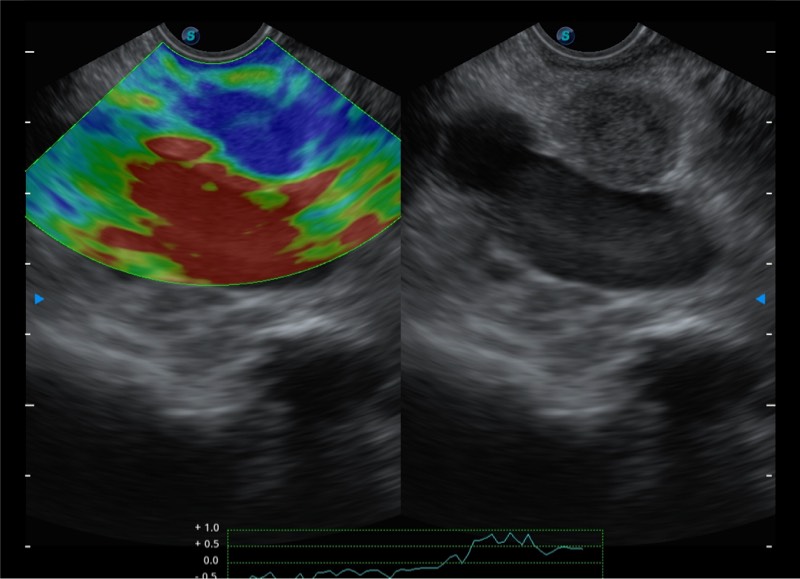

基于二十年的超声技术积累,乐玩lewin国际提供了最新一代的独立超声主机,在提供高质量图像的同时满足多学科使用。具备常见多普勒技术并提供弹性成像、声学造影等高端影像技术。新一代传感器具有更强的抗干扰能力并减少图像伪影。